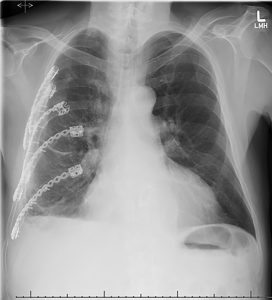

On the last day of June, Peltz and cardiothoracic surgeon Robert Meguid, MD, MPH, decided Custy couldn’t afford to let nature take its healing course. They turned to hardware to repair the fractures: horseshoe-shaped titanium devices fitted over the front and back of each rib and secured with screws. These “rib plates” also helped to stabilize Custy’s chest wall, Meguid said. He and Peltz also drained blood out of the pleural cavity, allowing the right lung to expand. In addition, they found that a shard of one of the fractured ribs had sliced his diaphragm, exposing a portion of his liver. They repaired that laceration during the procedure.

Less than two weeks after the surgery, Custy left UCH, weak and 20 pounds lighter, but free of chest tubes and supplemental oxygen. In early October he was still doing some physical therapy and managing what he described as “dullish” nerve pain and stiffness, but he said he now has the “prospect of normalcy.” He has gone back to horse riding and hopes to hit the ski slopes again this season with Carol.